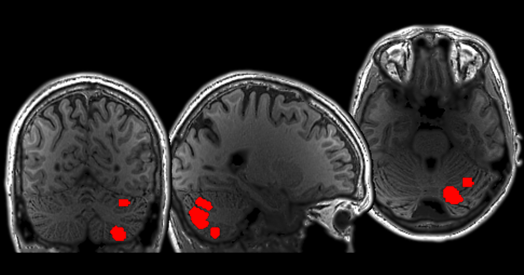

Cerebellum responds to language like cortical areas